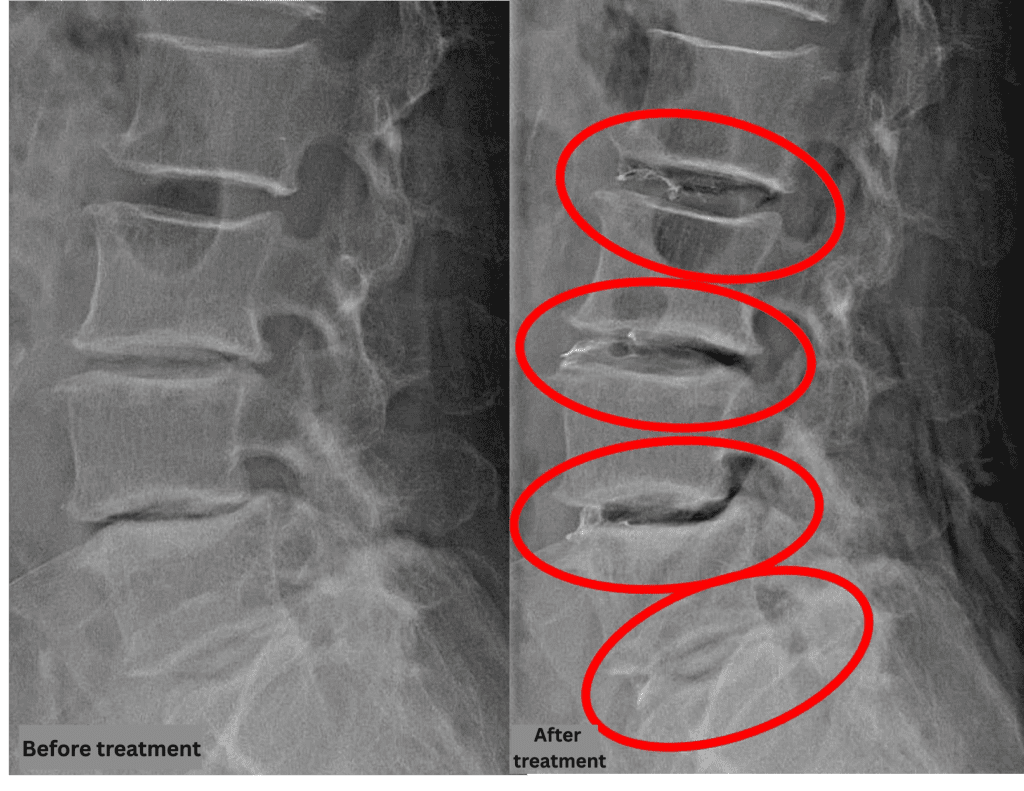

Imaging and findings

- L2/3, L3/4, L5/S: Disc degeneration

- L4/5: Disc degeneration, disc herniation, degenerative spondylolisthesis

The above findings were also observed on the imaging.

Compression of the spinal canal caused by disc abnormalities at L2/3, L3/4, L4/5, and L5/S was considered the most likely cause of the patient’s symptoms.

After consulting with the patient, the Cellgel Method was performed on L2/3, 3/4, 4/5 and 5/s.